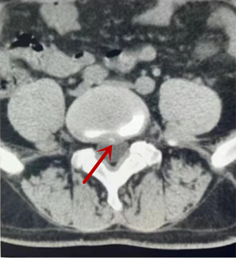

箭頭提示椎間盤突出